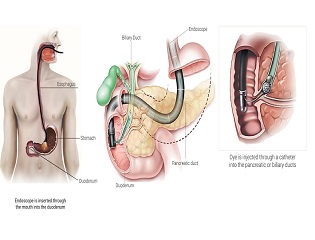

ERCP - Endoscopic Retrograde Cholangio - Pancreatography

Patients with UC are also at risk for extra-intestinal manifestations of UC (complications outside of the colon). These complications most frequently involve the liver, skin, eyes, mouth, and joints. Within the liver, patients with UC may develop primary sclerosing cholangitis. This occurs in about 3% of patients with UC. PSC can progress even if UC is not active and it is often detected by elevations in liver blood tests and confirmed by the use of MRI scans such as Magnetic Resonance Cholangiopancreatography (MRCP) or endoscopic procedures such as Endoscopic Retrograde Cholangiopancreatography (ERCP).